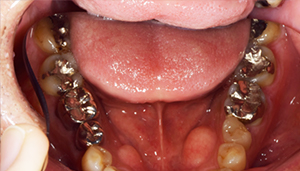

症例2

治療前

治療後

治療内容

奥歯はアマルガムという発ガン性があると言われている銀の素材を金銀シルバーインレーに変えました。前歯は金属を使用した歯でややまわりのご自身の歯より色がういていたので、周りの歯にあわせて透明感のある仕上がりのある材料にてやり変えました。

治療期間 1ヶ月

治療費 合計:990,000円 (内訳)

ジルコニアボンド:165,000円×6本

治療のリスク・副作用 被せ物を外すと、ご自身の歯が少ない場合は別途はを残すための処置が必要になることがあります。